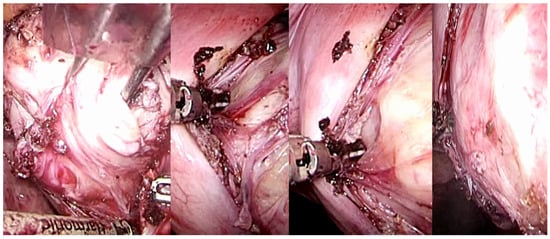

Uterine fibroids, during their growth, facilitate the progressive development of a peripheral surgical-anatomical biological structure known as myoma pseudocapsule [,]. This anatomical entity, which remained largely unrecognized for numerous years, has garnered significant interest among gynecologists specializing in fertility surgery in the contemporary century. This biological structure arises from the compression of the surrounding myometrium by the fibroid, creating a separation, albeit minimal, between the fibroid and the healthy myometrium. In succinct terms, the pseudocapsule displaces the intact myometrial muscular fibers, functioning as a delicate fibromuscular barrier, thereby preserving the integrity and contractility of the uterine musculature. Moreover, from an anatomical perspective, the uterine fibroid is structurally linked to its pseudocapsule via connective bridges; however, it is devoid of its own true vascular pedicle and, on occasion, possesses vascular and collagen fiber bridges that anchor the myoma to the myometrium, thus disrupting the surface of the pseudocapsule [] (Figure 6).

Figure 6.

Laparoscopic image of intracapsular myomectomy. From left, progressive identification of the fibroid (in white, hooked with Collins’s forceps) with the pseudocapsule branches covering it and subsequent incision of the fibrovascular branches of the pseudocapsule to detach and enucleate the fibroid from the pseudocapsule, with minimal blood loss and less myometrial damage.

This arrangement culminates in the establishment of a distinct cleavage plane that exists between the myoma and the pseudocapsule, commonly referred to as the cleavage plane. Biologically speaking, the myoma pseudocapsule exhibits a bio-structural composition analogous to that of the myometrium.